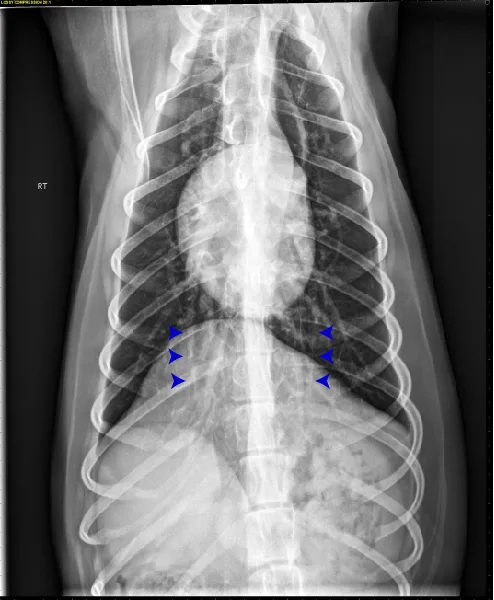

At least 2 orthogonal views, ideally taken during peak inspiration, are necessary for appropriate radiographic study of the cardiovascular system; however, a 3-view study is ideal for comprehensive evaluation of the thorax. Some differences should be considered when deciding to acquire a right versus left lateral projection and a dorsoventral (DV) versus ventrodorsal (VD) projection. On the left lateral view, the cardiac silhouette is typically more rounded and the apex is further elevated from the sternum than in the right lateral view (Figure 1). In the DV view, the cardiac silhouette is commonly displaced cranially and to the left by the diaphragm and appears more rounded than in the VD view. The caudal pulmonary vasculature is better delineated in the DV view, whereas the lung field (particularly the accessory lobe) is better evaluated in the VD view (Figure 2).

FIGURE 2 Normal DV (left) and VD (right) projections of the thorax in a large, crossbreed dog. The cardiac silhouette appears more rounded, and the caudal pulmonary vasculature is more apparent (arrowheads) in the DV view compared with the VD view. In some DV projections, the cardiac silhouette can appear significantly displaced to the left (not apparent in this case). Images courtesy of Federico Villaplana Grosso, DACVR, DECVR